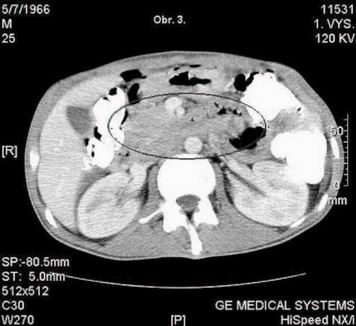

Pacient absolvuje CT vyšetření, kde je popsána velmi suspektní metastáza vpravo subpleurálně, na rozhraní S 9/10 - obr. 1., dále v retroperitoneu paket patologických uzlin 27 x 23mm - mezi aortou a dorzální plochou pankreatu, v úrovni dolního okraje pankreatu. obr. - 2., 3., 4. CT plic zobrazilo v mediastinu jen několik drobných uzlin nad bifurkací, velikosti do 9 mm. Nejsou vzhledu charakteristického pro patologické uzliny. V plicním parenchymu vpravo v S 10 subpleurálně metastatické ložisko velikosti 2O mm, polokulovité zesílení pleury kraniálně v S 1O vpravo - obr. 1. a suspektní drobné subpleurální ložisko velikosti cca 5 mm vpravo v S 2. Vlevo bez ložiskových změn, bez fluidothoraxu. Hodnoty tumormarkerů nepřesahují referenční meze - CEA 2.7 ug/l (referenční hodnota do 4.6), CA 19-9 < 2 kU/l (referenční hodnota do 37.0).